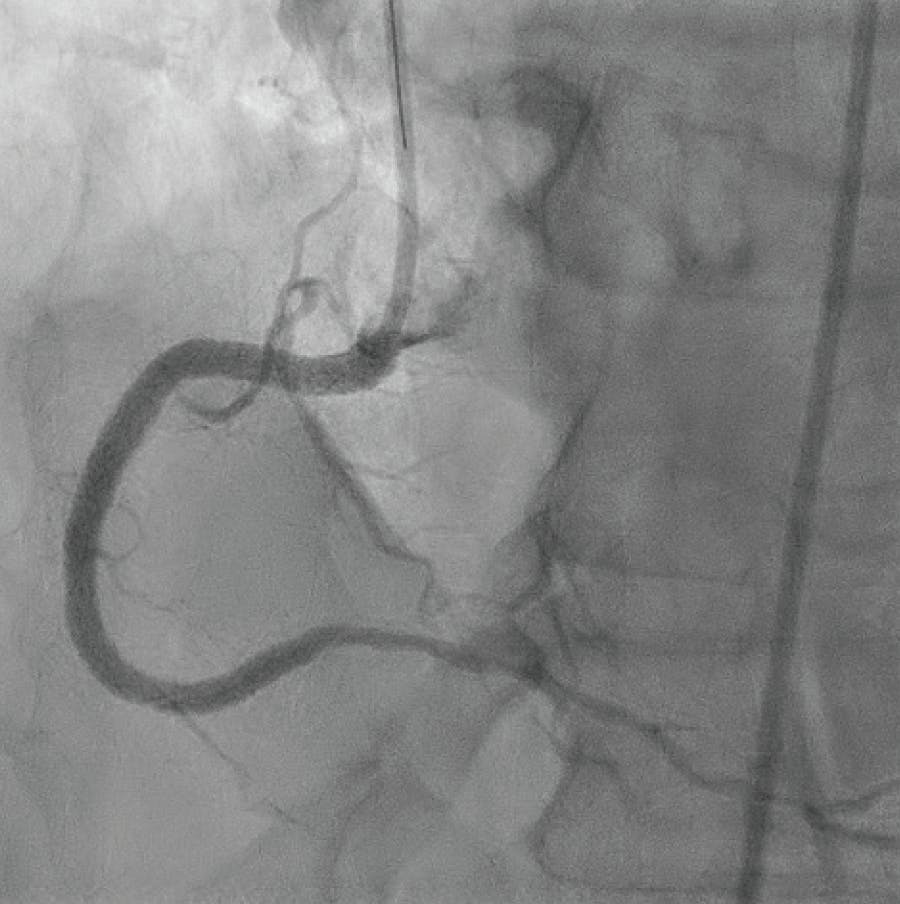

Next, a SION Black wire (Asahi Intecc USA, Inc.) was utilized to access the posterior descending artery (PDA) via the LAD to RCA collateral network despite significant tortuosity, with good 1:1 torque with the Speed-Torque® novel torque device. A JR guidewire was utilized to access the RCA for antegrade access. The PDA retrograde wire placement (Figure 5) allowed for target positioning of an antegrade Hi-Torque Pilot 200 wire from the proximal RCA to cross the lesion and position it in the PDA to complete the intervention. The antegrade access was gained to the PDA with the back support of a Corsair microcatheter and good 1:1 torque with the Speed-Torque® device. Balloon angioplasty was completed to the RCA with a 2.0-mm balloon. IVUS images were obtained for vessel detail and stent sizing. Successful stent placement was completed to the RCA with three overlapping Synergy stents measuring 3.5 X 48 mm, 4.0 X 32 mm, and 5.0 X 8 mm from distal to proximal (Figure 6). The patient continued antiplatelet therapy with prasugrel 10 mg once daily along with acetylsalicylic acid 81 mg once daily and guideline-directed medical therapy, including b blockade, angiotensin receptor blocker, and statin therapy. The patient was discharged to home on day 1 after multivessel intervention without complications and asymptomatic.

Figure 5. Antegrade and retrograde RCA wire positioning.